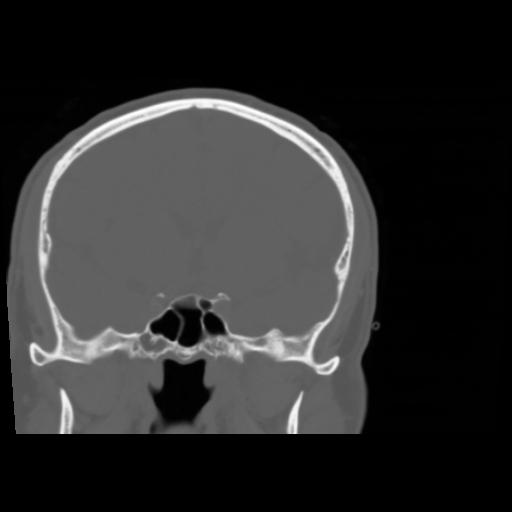

5 CEREBRO,,Coronal,3.000,CEREBRO,Coronal,